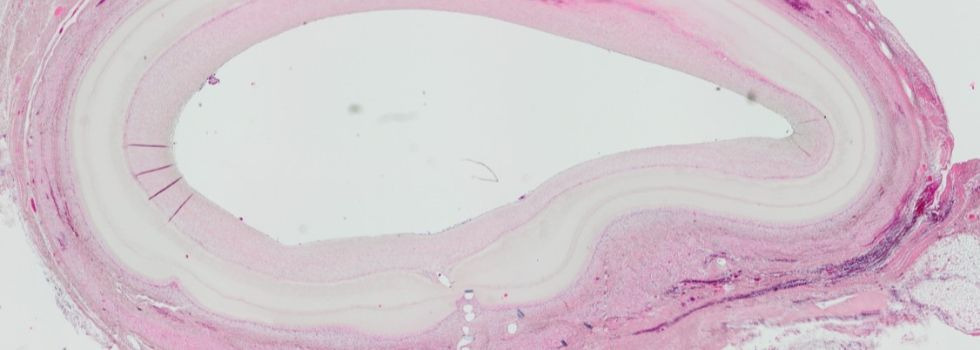

Artificial Bypass - Tissue Engineering in Cardiac Surgery

With a share of more than 50%, bypass surgery represents the largest share in the cardiac surgery portfolio. Every year alone in the US and Germany together… more.